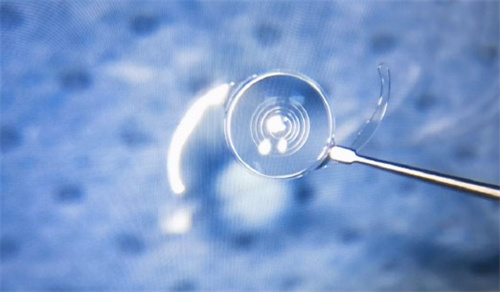

白内障手术是一种非常常见且安心的眼科手术,通常采用超声乳化技术将模糊的晶状体取出,然后植入人工晶状体以改善眼部视力。